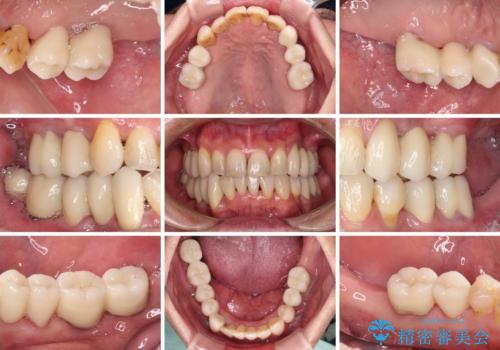

- 歯並びやグラグラする奥歯など、気になる所を全部治したいとのことで来院された患者様です。

奥歯は咬み合わせや歯周病により歯槽骨が失われていたり、むし歯や破折している歯などがあったりと、歯周病治療やインプラント補綴、矯正治療など、総合的に治療が必要と診断されました。

まずは歯周病治療やインプラント埋入を行い、環境が整った後にワイヤーを併用したインビザライン矯正を行い、オールセラミッククラウンにて補綴治療を行うこととしました。

初診時に4年かかりますとお伝えし、実際に4年数ヶ月を要する治療となりました。

治療中は仮歯が頻繁に脱落したり、歯周外科によりむき出しとなった歯根が知覚過敏を起こしたりと、苦労は絶えませんでしたが、4年の治療の後にスッキリと仕上げることができました。